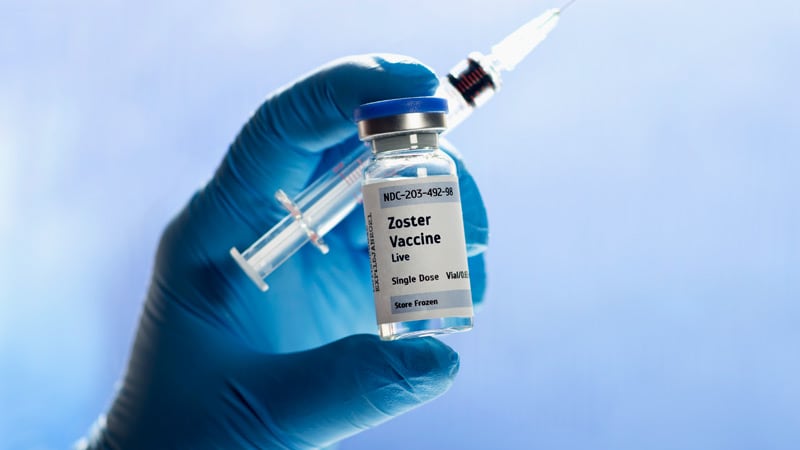

Медицинские снимки и изображения опоясывающего герпес вируса

Раздел: Фотодневник открытий